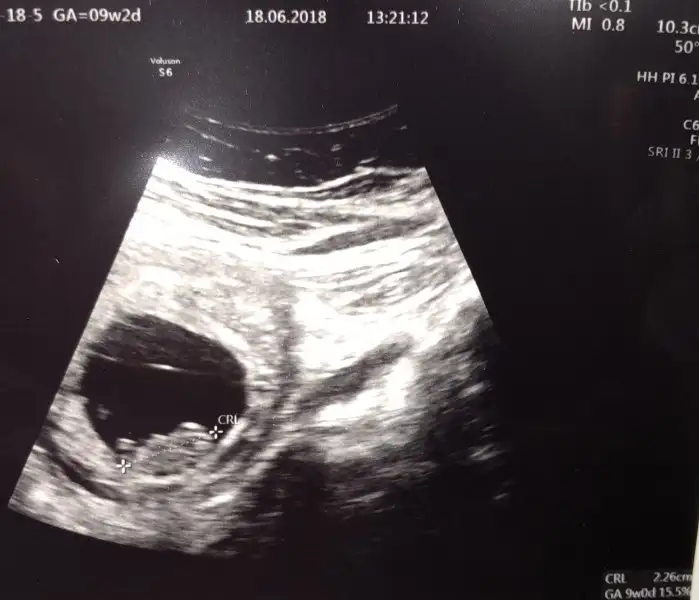

Maşallah masallah minigineMerhaba, bugün miniğimi gördüm kalbi gümbür gümbür atıyordu çok şükür haftasıyla da uyumluymuş birazcık da hareketlenmeye başlamış. 2.3 cm olmuşuz insanın aklı şaşıp kalıyor minicik bedende atan kalp sesini duyunca subhanAllahDarısı isteyen bekleyen herkese olsun